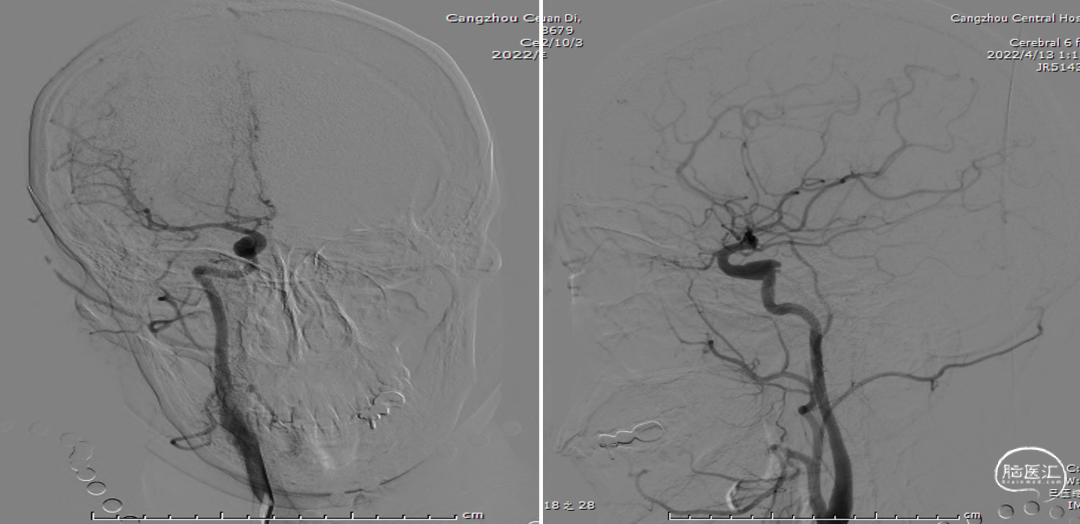

术后复查右颈内动脉造影(2022-12-27)

术后复查右颈内动脉3D重建

复查左颈内动脉造影(2022-12-27)

术后3D重建

术后3D图像及透视

术前、术后3D图像对比